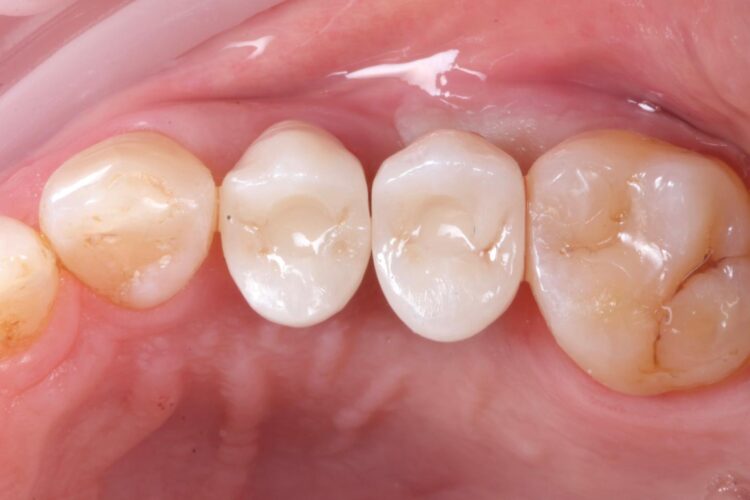

The implant in the UL5 was uncovered 3 months later to reveal healthy tissues. Three weeks later the final scan was taken (using trios intra-oral scanner) for the fabrication of the definitive crowns. On the day of crown fits both abutments were removed and the crowns seated. Due to the UL4 site having a custom healing abutment, which had been supporting our ideal emergence profile, it was much easier to engage this restoration and seat within the already moulded soft tissues.

With regards to the UL5 there was some blanching around the buccal aspect of the crown due to the use of a generic abutment, which does not offer any resemblance to the ideal emergence profile for the final restoration. Regardless good prosthetic positioning had been achieved to allow for screw-retained restorations in both implants. The final restorations were fitted as single unit layered zirconia crowns on titanium bases. The patient was delighted with the results.

Upon reflection of this case, a custom healing abutment may have delivered better soft tissue contouring than the generic abutment on the UL5. Healing may have taken longer, but it would have been easily tolerated by the patient and may have resulted in a better biological result with optimised aesthetics.